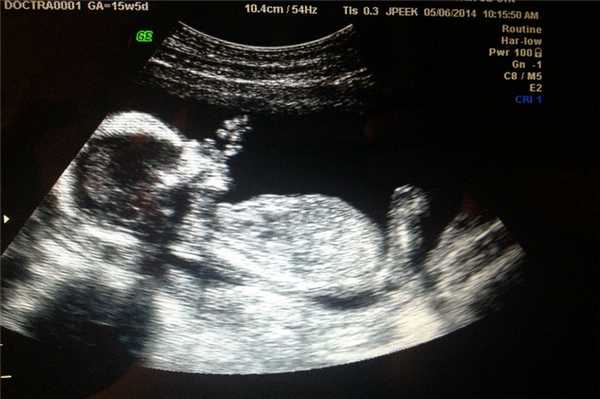

Фото УЗИ ребенка на разных сроках беременности

Если беременность желанная, будущие родители внимательно относятся к пренатальной диагностике плода. Чтобы убедится, что ребенок развивается нормально, в течение 9 месяцев гинеколог несколько раз направляет женщину на ультразвуковое исследование. Фото УЗИ может многое рассказать врачу и будущим родителям о малыше. Кроме того, снимок станет трогательным напоминанием для семейного архива.

Чтобы сделать фото УЗИ малыша на разных сроках, беременной женщине необходимо записаться на ультразвуковой скрининг в медицинском центре «Диана».

Фото УЗИ ребенка на 15 неделе беременности

В этот период происходит активное развитие головного мозга и опорно-двигательного аппарата. Несмотря на то, что глаза малыша по-прежнему закрыты, он реагирует на свет.

На УЗИ размеры малыша достигают 10 см. Ребенок глотает амниотическую жидкость, может сосать пальчик за счет формирования сосательного рефлекса. Движения плода активные, но хаотичные.